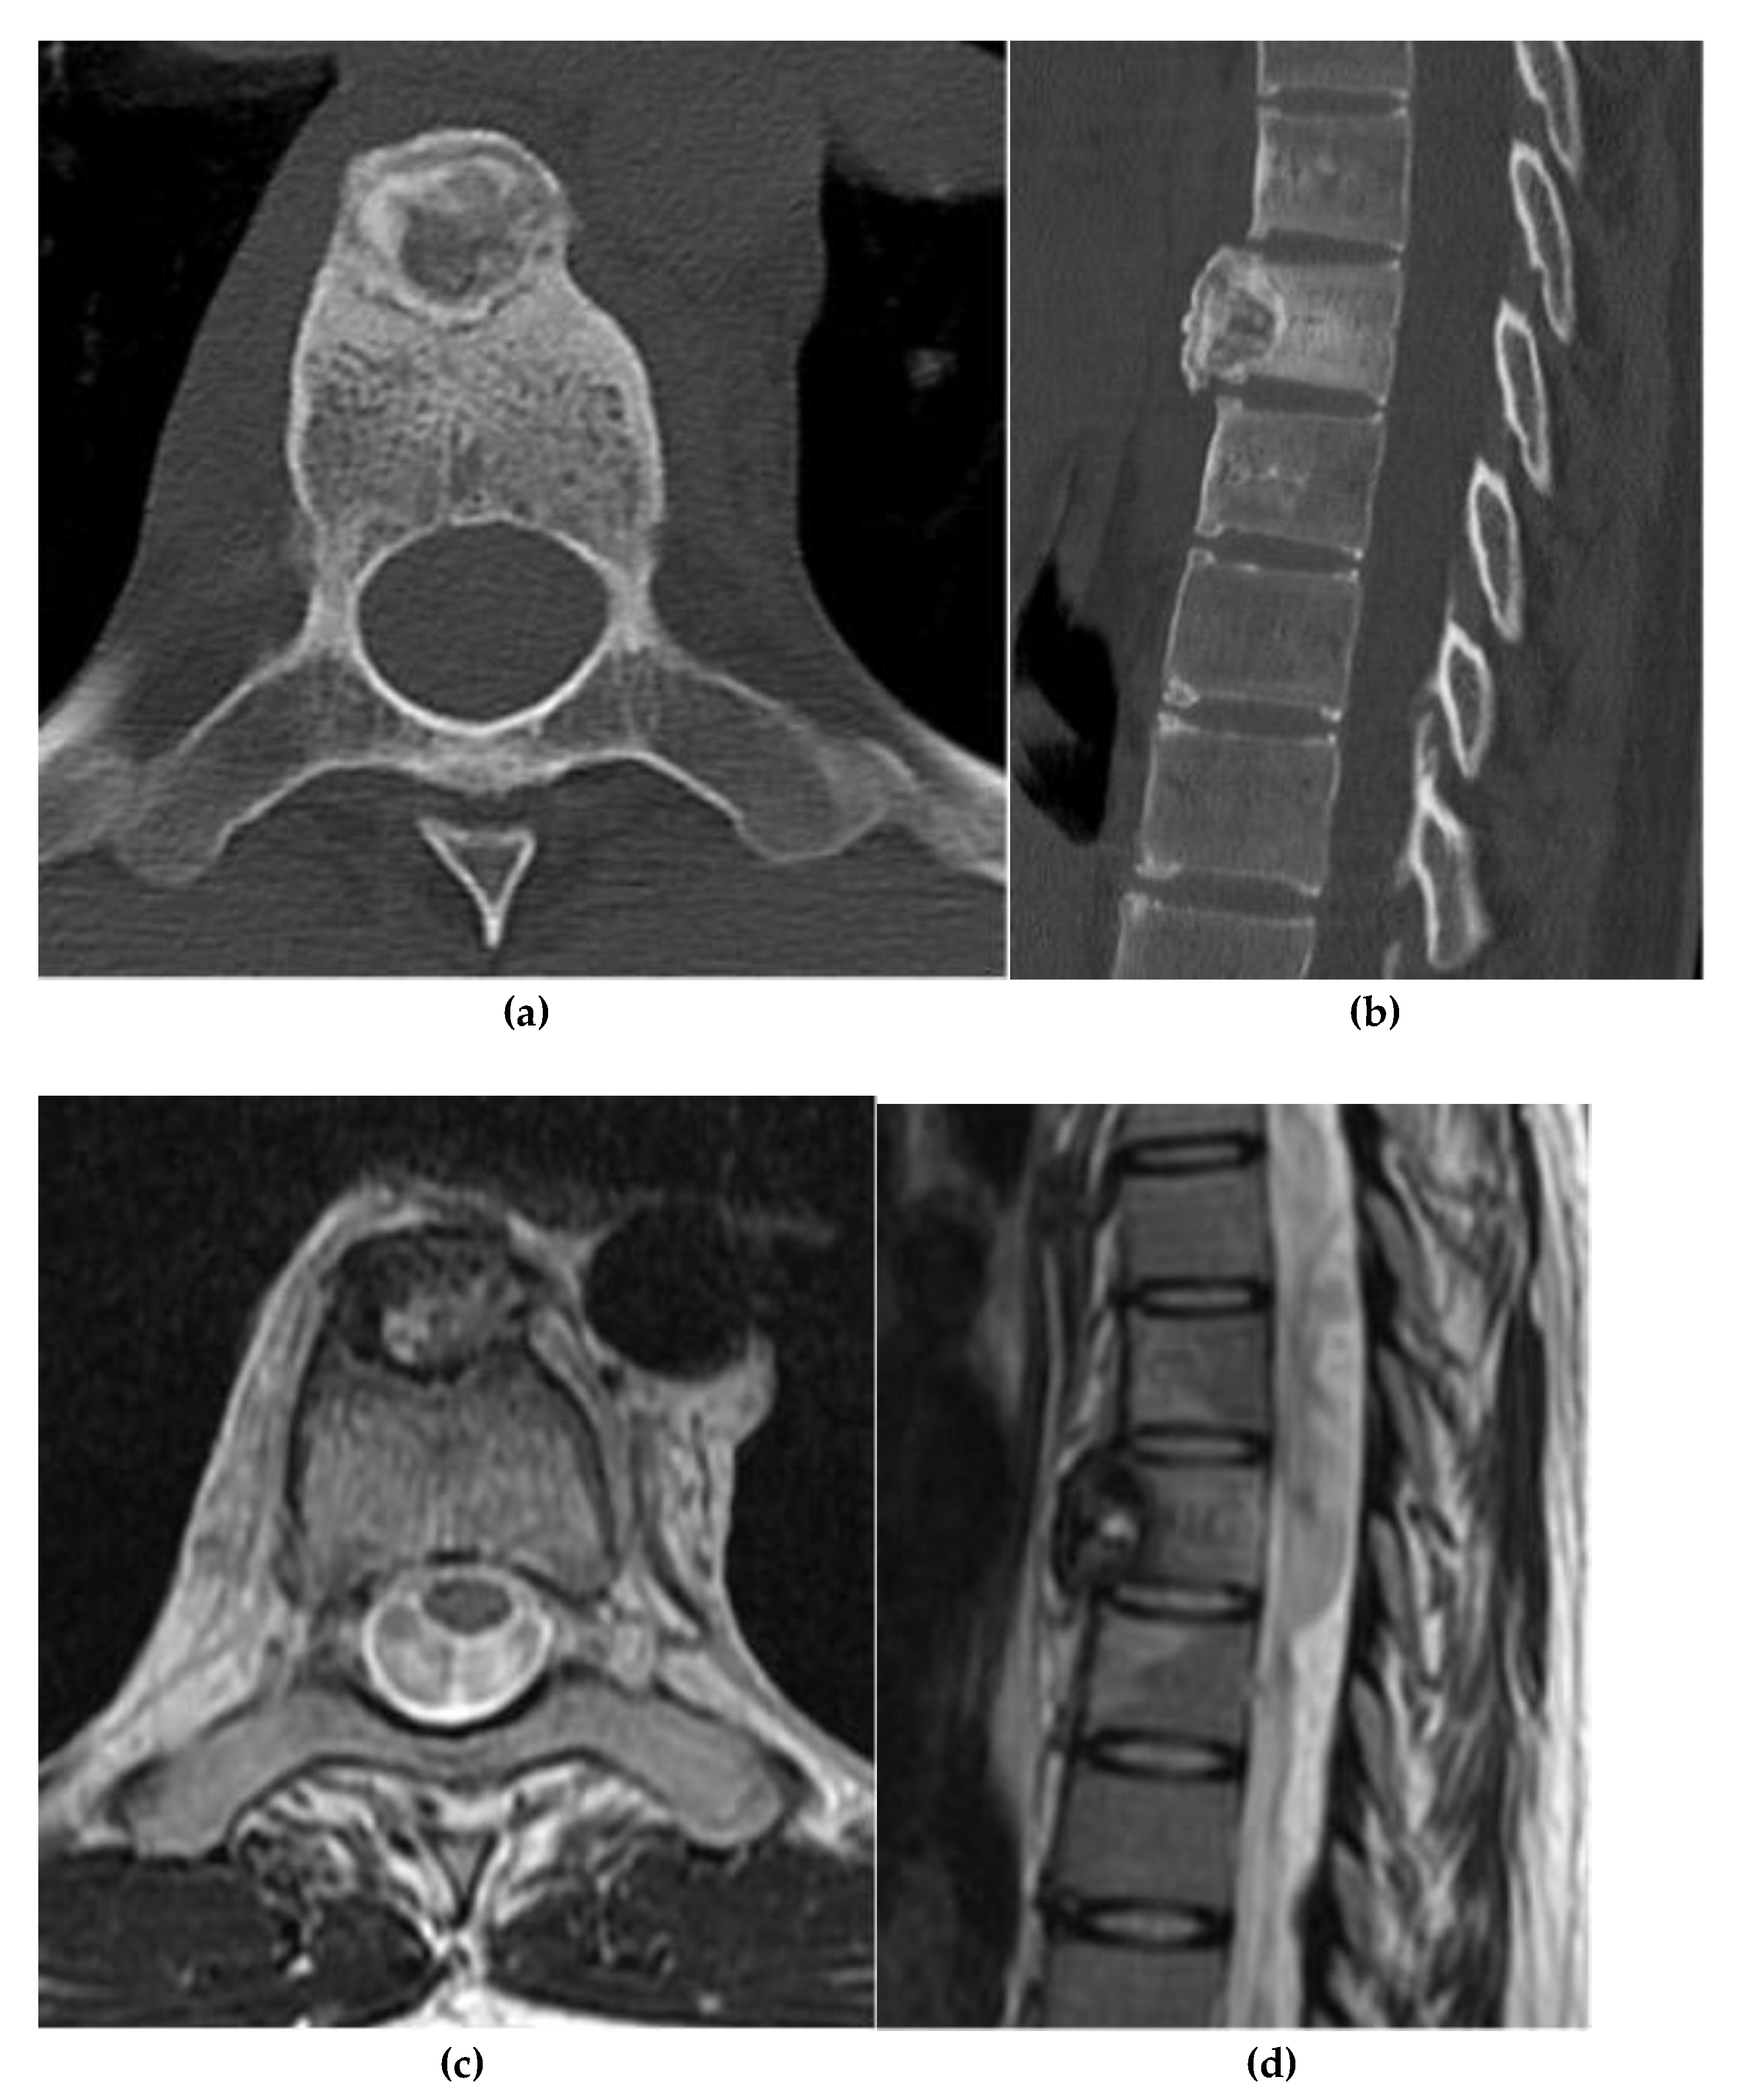

Chordoma

4. Hematolymphoid